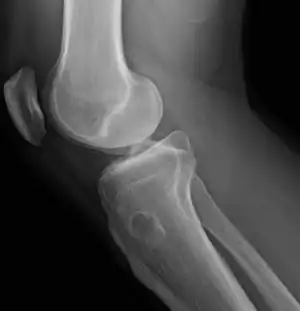

| Osteochondroma, a common type of non-cancerous chondrogenic tumors | |

| Osteochondroma[2] | ![]() | |